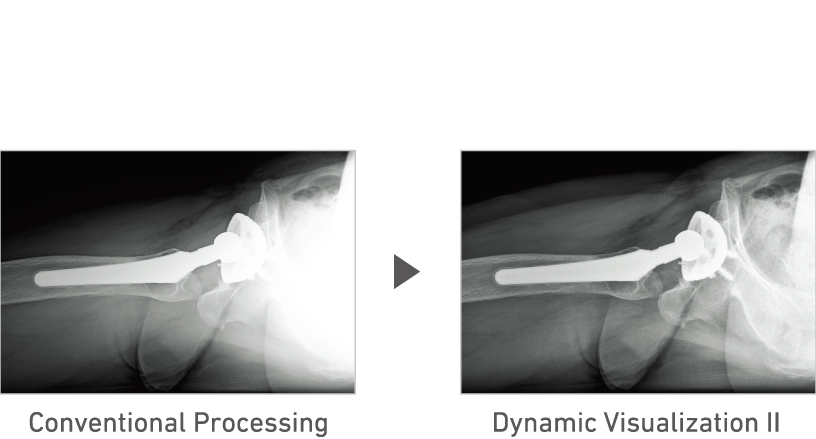

FDR D-EVO III utilizes the latest Fujifilm digital image processing technologies including Dynamic Visualization, which optimizes image display based on monitor characteristics and FNC noise suppression processing that improves image quality, automatically extracting and separating noise components in the image.

Advanced recognition algorithms automatically adjust contrast and density for individual body parts based on calculation of estimated 3D image data. (Option)